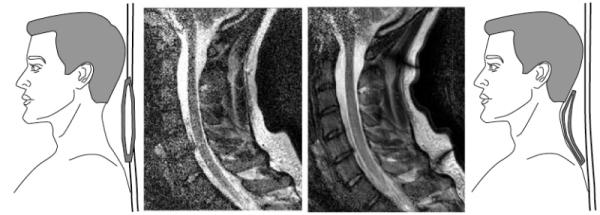

Команда ученых из Калифорнийского университета разработала гибкую катушку для магнитно-резонансной томографии: в будущем эта технология позволит уменьшить время каждого обследования и повысить диагностическую точность.

Разработанная радиочастотная катушка для МРТ выглядит как одеяло, которым можно плотно обернуть пациента. Авторы проекта уверяют, что прилегание поверхности устройства к телу обследуемого повысит чувствительность томографии и позволит получить лучшие изображения за меньшее время.

Гибкие катушки, созданные по технологии трафаретной печати, гораздо легче, и могут быть подогнаны под тело каждого конкретного пациента. Использоваться новая разработка будет с томографами с индукцией магнитного поля в 1,5 и 3,0 Тл. Опыты показали, что магнитно-резонансная томография, сделанная с использованием гибкой катушки, дает лучшее изображение и уменьшает количество артефактов на нем.